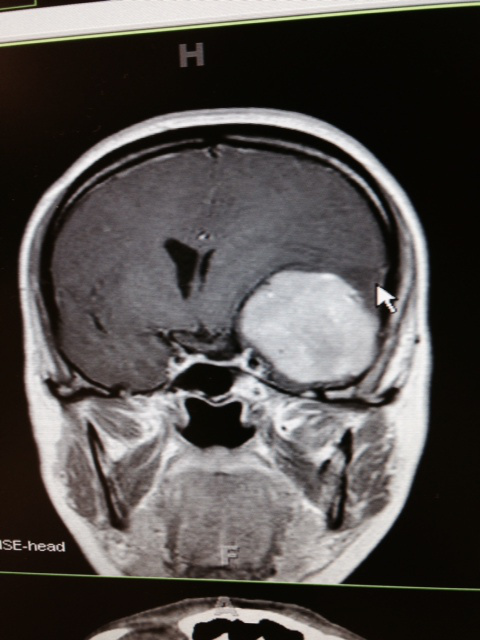

I write this as I am flying to Nashville to join my parents and siblings to be there for my sister’s brain surgery. Even as I type this, it still is pretty surreal. As I was preparing for service two weeks ago, I received a call from my sister explaining that they found a tumor the size of a racquetball in the meningeal area between her brain and skull. There were tears, a promise to talk more the next day and the statement, “I’ll send you a picture.” It was the one above…and when I saw it for the first time, I gasped.